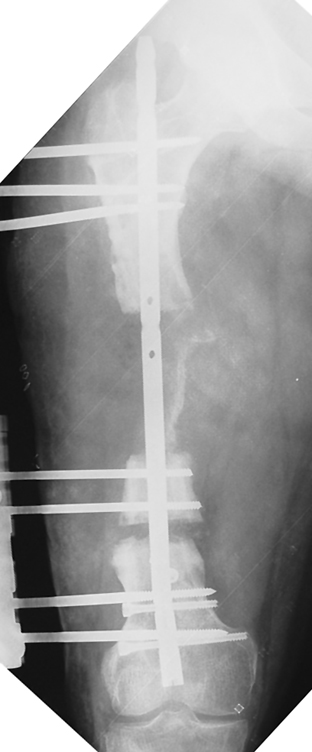

Uygun radikal debridman tüm nekrotik kemik ve yumuşak dokuların çıkartılmasını gerektirir, ve sıklıkla uzuvda instabiliteye neden olur. Kalan kemik ve yumuşak doku defektinin bir şekilde fiksasyonu ve rekonstrüksiyonu gereklidir. İlizarov’un ortaya koyduğu distraksiyon osteogenezi yöntemi, kaynamanın elde edilmesi, deformitenin düzeltilmesi, bacak boy eşitsizliğinin giderilmesi ve segmental defektlerin rekonstrükte edilmesi için başarıyla kullanılmaktadır.

Eksternal fiksatör ile geçen süre (eksternal fiksasyon indeksi), gereken distraksiyon miktarına bağlıdır ve bu süre boyunca bazı komplikasyonlarla karşılaşılabilir. Distraksiyon dönemi sona erdikten sonra, distraksiyon süresinin iki katını aşan konsolidasyon döneminde hastalar eksternal fiksatörü zorlukla tolere edebilirler. Yeterli konsolidasyon sağlanmadan eksternal fiksatör çıkartılırsa ise kırıklar, deformite ve kısalık oluşabilir. Hastanın fiksatör ile birlikte geçirdiği sürenin azaltılması ve böylece hasta konforunun ve aktivite düzeyinin arttırılması için intramedüller çivi üzerinden uzatma yöntemi uygulanmaktadır. Bu yöntemde distraksiyon dönemi sona erdiğinde kemiğin içindeki çivi statik olarak kilitlenmekte ve eksternal fiksatör çıkartılmaktadır. Stabilizasyon intramedüller çivi tarafından sağlandıktan sonra konsolidasyon dönemi gerçekleşmektedir. Bu şekilde hem eksternal fiksatörün uzun süre kalmasından hem de erken çıkartılmasından kaynaklanan komplikasyonların önüne geçilmektedir.

Vaka 2